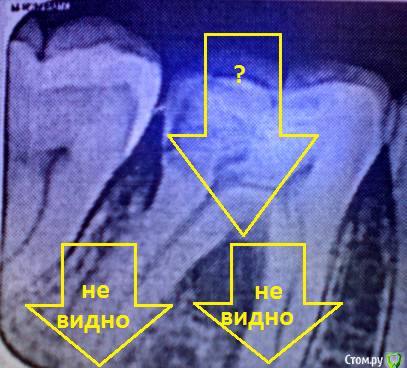

___49___ Опубликовано 6 декабря, 2016 Поделиться Опубликовано 6 декабря, 2016 (изменено) Обратите внимание на участок между корней - под "?", и на снимке нет верхушек корней - "не видно". на десне свищ - не критично (не т ничего экстренного) но надо решать от куда он. Изменено 6 декабря, 2016 пользователем ___49___ 1 Ссылка на комментарий

talyan Опубликовано 6 декабря, 2016 Автор Поделиться Опубликовано 6 декабря, 2016 так каналы не пломбировали чтоли?, бугорок ваш на против 6-ки, по снимку там кариозная полость сообщающаяся с полостью зуба то есть с пульпой, если пломбировки каналов не было ее нужно провести, и да нужен качественный рентгеновский снимок причинного зуба с видимой зоной вокруг верхушек корней. И четко пясните снимок ваш до или после лечения?Зуб пломбировали, как раз примерно через неделю, бугорок появился. Снимок, это уже после лечения.Как понимаю, не качественно запломбировали или занесли что-то? Обратите внимание на участок между корней - под "?", и на снимке нет верхушек корней - "не видно". на десне свищ - не критично (не т ничего экстренного) но надо решать от куда он. Понятно, благодарю.Вобщем, только хирург очно сможет конкретнее сказать? (от терапевта конкретики не было). А свищ получается, надрезом убирается? Ссылка на комментарий